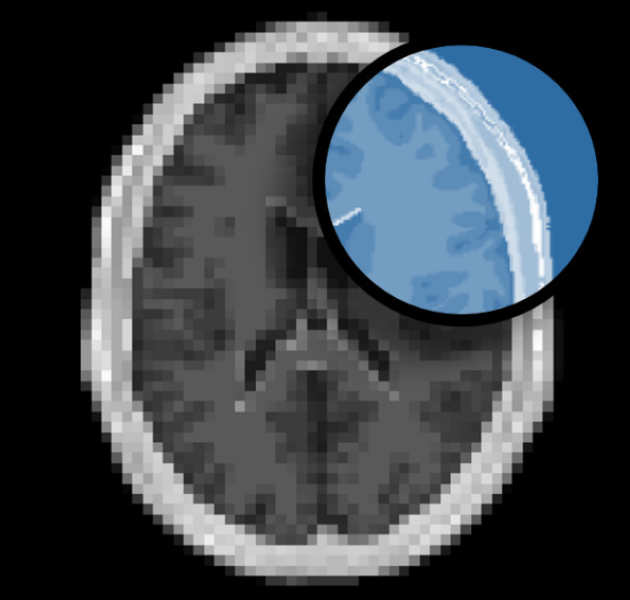

Super-resolution

We are developing new methods to enhance spatial resolution in MRI.

We are developing new methods to enhance spatial resolution in MRI.